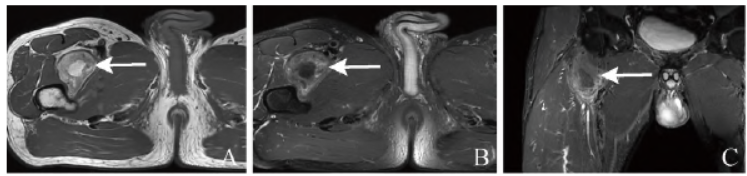

男,57岁,主诉:4个月前查体发现右侧髂腰肌及邻近肌间隙占位,无明显不适,肿物生长缓慢,呈逐渐增大趋势。体格检查:髋关节屈伸无明显受限,右侧髂腰肌下段内可触及一包块,无明显压痛,与周围组织界限清楚,浅表无静脉怒张,局部皮温不高,右下肢感觉肌力正常。MRI检查(图1A~D)提示脂肪肉瘤

可能。CT(图1E)提示含脂类肿瘤。

术中见右侧股骨上段前方肌间隙内肿物,大小约7.0 cm×5.5 cm×3.5 cm,表面呈灰红灰黄色,部分切面淡黄,部分切面灰黄;肿物周围附包膜,包膜完整,与周围组织界限不清。病理见图1F。免疫组化:S-100(+)、CD34(血管+)。最终诊断为冬眠瘤。

图1 男,57岁,右侧股骨上段肌间隙内冬眠瘤。轴位T1WI见右侧股骨上段前方肌间隙内团状高或稍低信号(箭,A),大小约7.7 cm×4.6 cm×4.7 cm,边界欠清,邻近肌肉软组织呈受压、移位改变,双侧股骨形态、信号未见明显异常;轴位T2WI脂肪抑制见病灶呈不均匀低信号(箭,B);冠状位T2WI见病灶信号呈类圆形(箭,C);增强扫描呈不均匀强化(箭,D);CT平扫

示右侧股骨前缘见团状脂肪密度影,其内密度不均,形态欠规整,CT值约为-8~61 Hu(箭,E);显微镜下见圆形、多角形细胞团,部分胞质内见嗜酸性颗粒及小脂滴,细胞核小而居中(HE,×100,F)